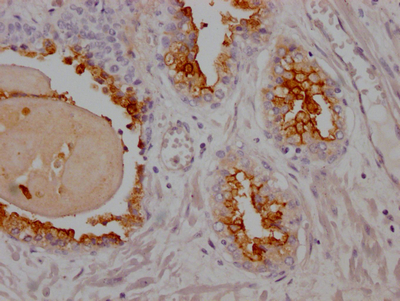

IHC image of CSB-RA162924A0HU diluted at 1:100 and staining in paraffin-embedded human prostate cancer performed on a Leica BondTM system. After dewaxing and hydration, antigen retrieval was mediated by high pressure in a citrate buffer (pH 6.0). Section was blocked with 10% normal goat serum 30min at RT. Then primary antibody (1% BSA) was incubated at 4℃ overnight. The primary is detected by a Goat anti-rabbit IgG polymer labeled by HRP and visualized using 0.05% DAB.